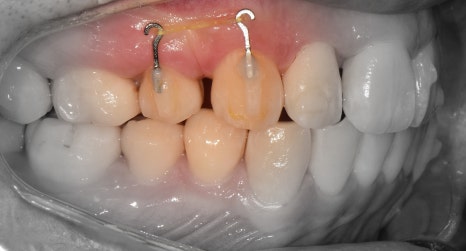

『발치 및 장치 부착, 인비절라인 진행』

표시를 해 둔, 갈고리처럼 생긴 것들은

Power arm 이라는 것들입니다.

이는, 치아들을 계획 했던 대로 정확히

이동을 시키게끔하는 보조수단으로 쓰입니다.